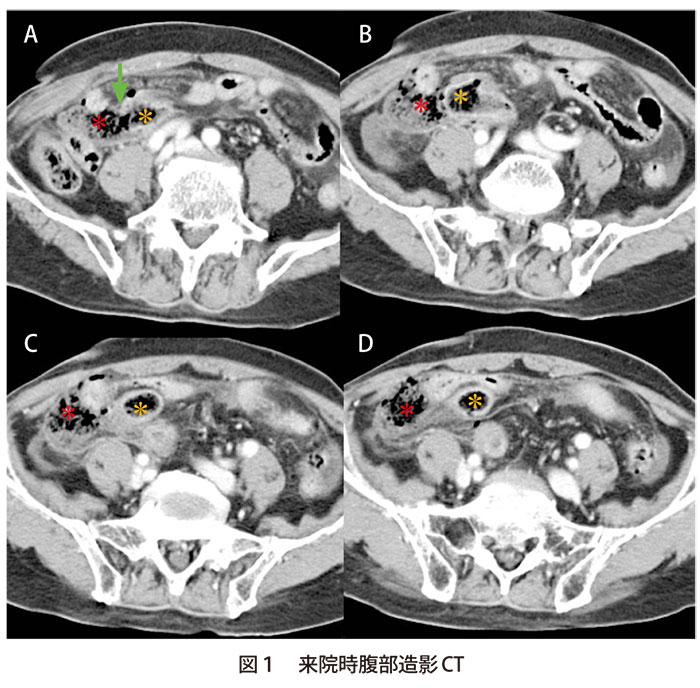

イレウスチューブの挿入経路と留置部位 イレウスチューブは胃管同様に経鼻的に挿入され、その先端はトライツ靱帯を越えて空腸以深に留置するのが基本である()。